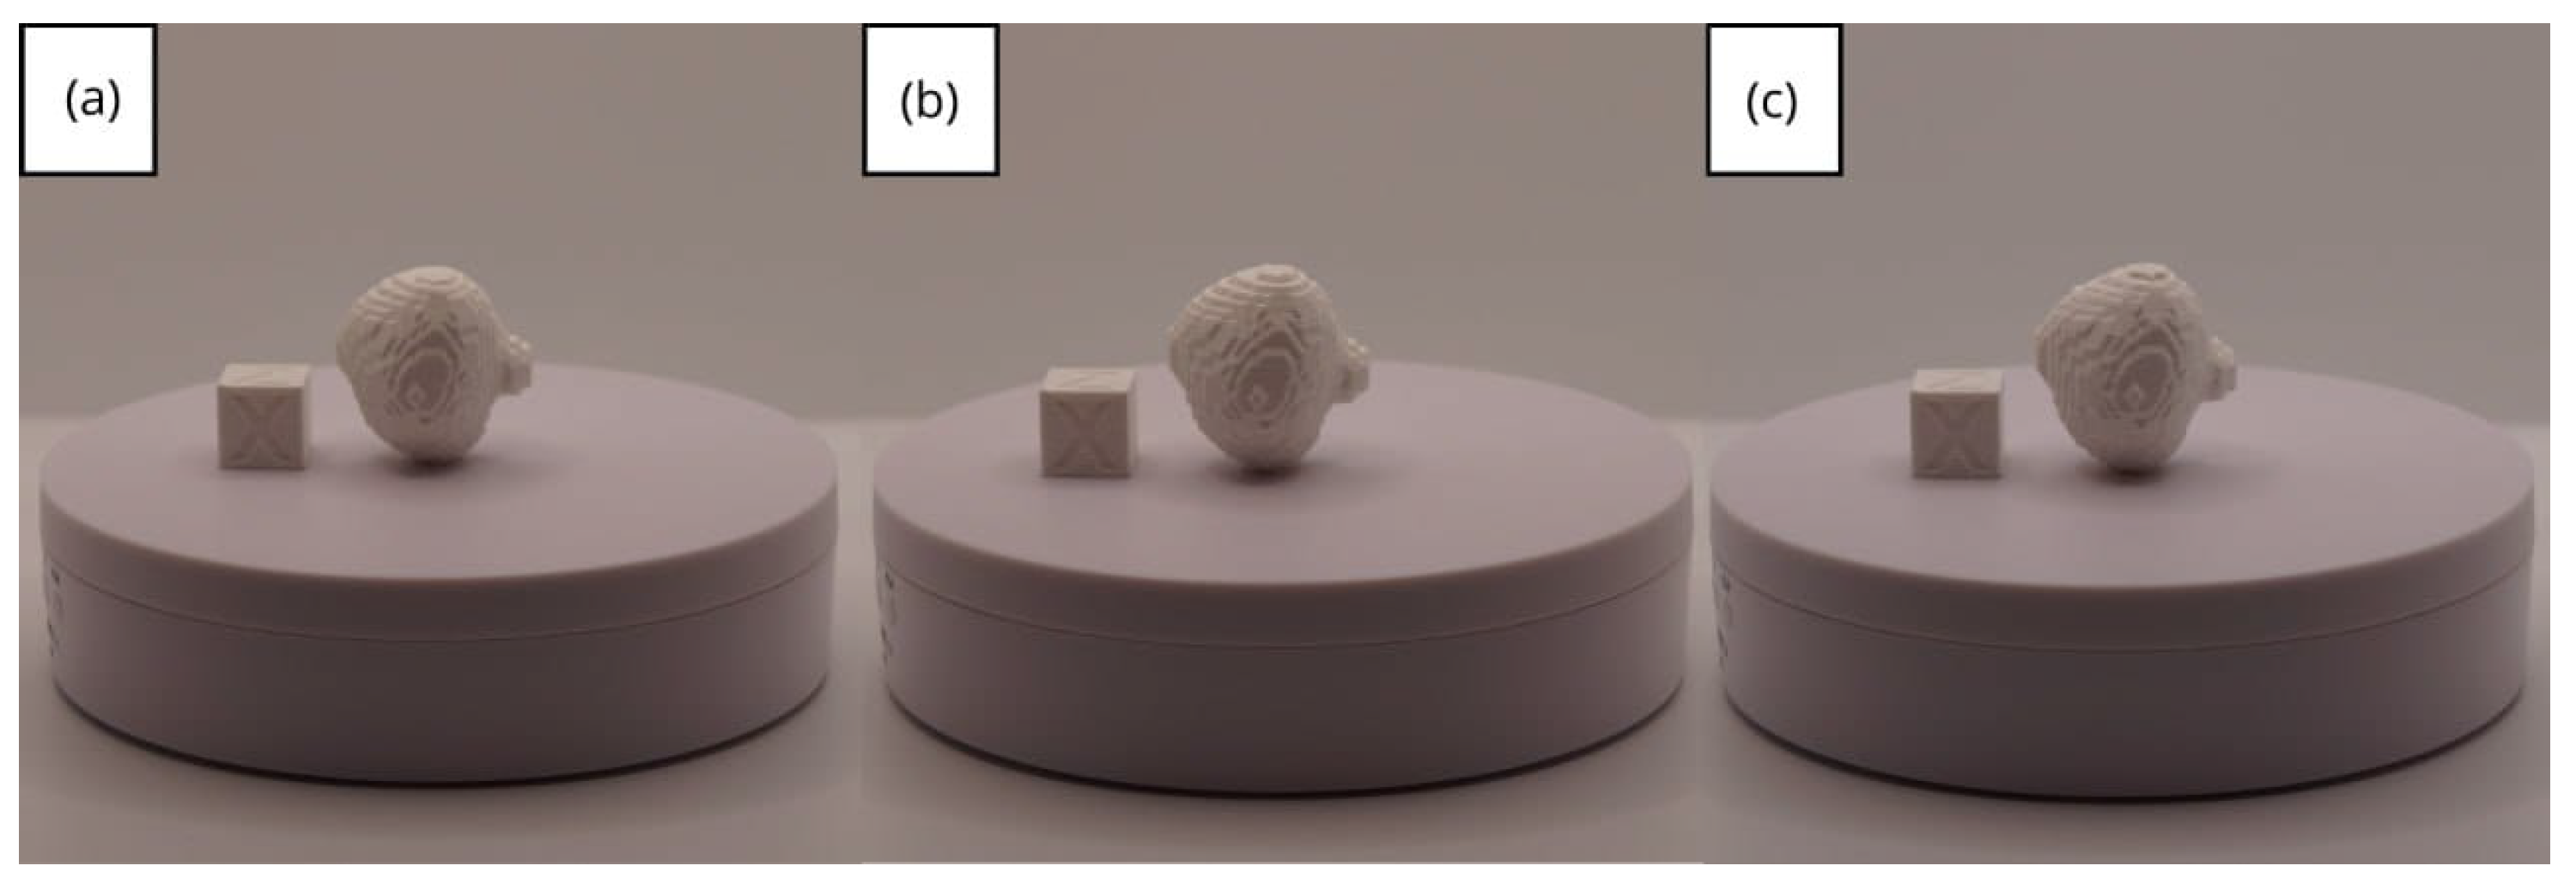

3.1.3. Final Printing

3.2. Human Lower Jaw

3.2.3. Final Printing

3.3. Human Brain Tumour

3.3.3. Final Printing